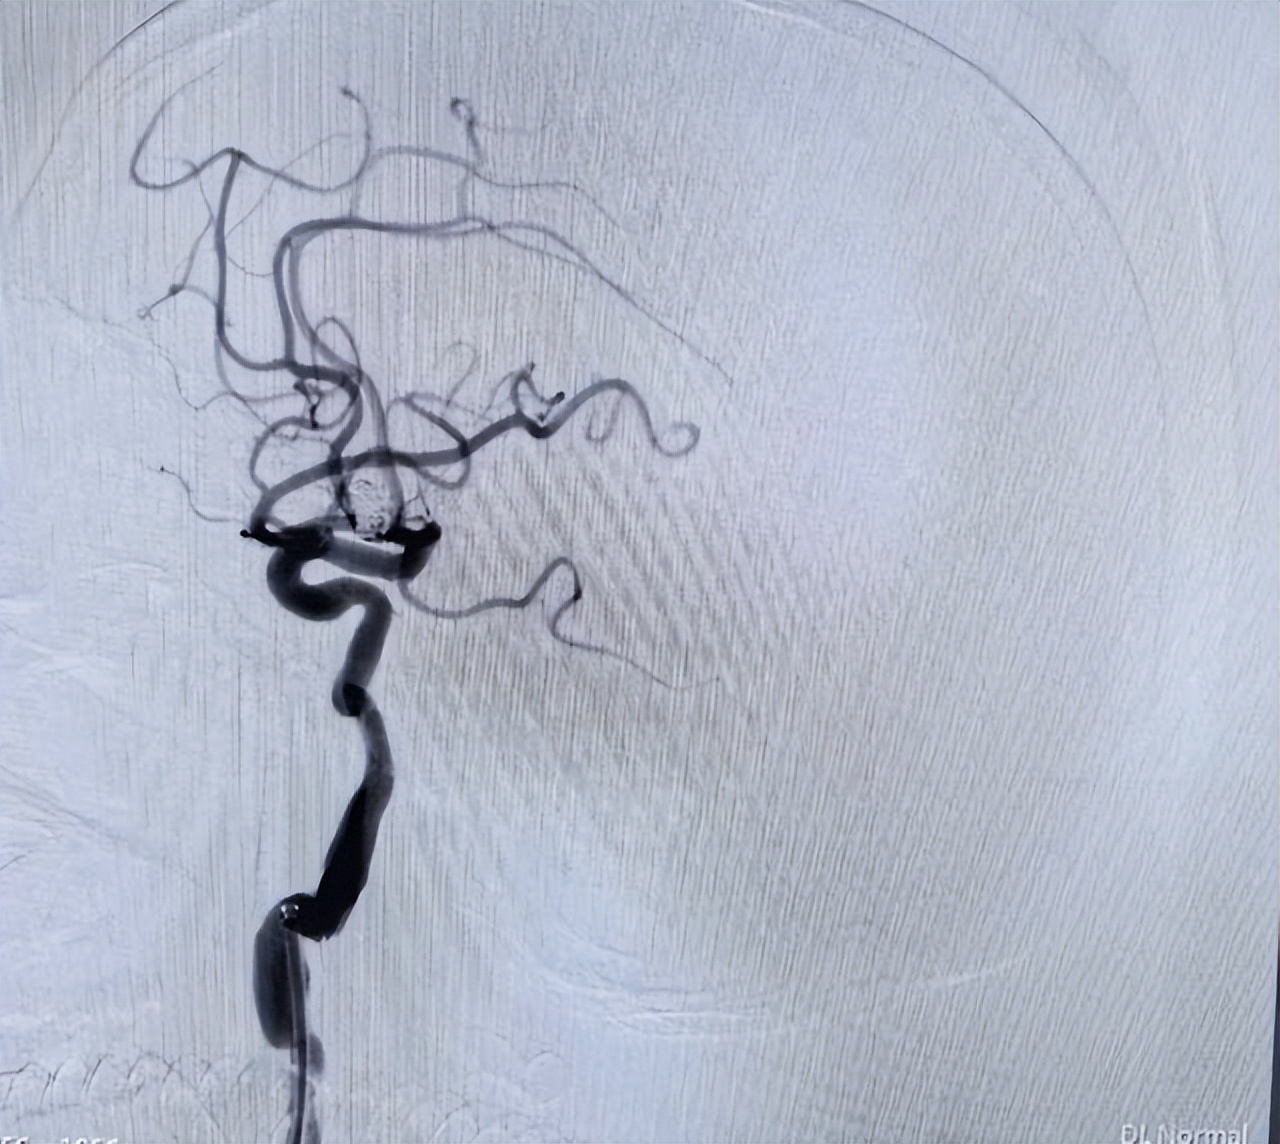

术中造影显示,刘女士的动脉瘤直径达8.5mm×7.0mm,形态复杂,尖端呈血泡样,这是动脉瘤中最凶险的类型之一,随时可能再次破裂!凭借精湛的技术和丰富的经验,专家团队沉着应对,成功实施“支架辅助弹簧圈动脉瘤栓塞术”,将这颗“炸弹”彻底“拆除”!

△术后影像

经过紧张的手术和术后监护,刘女士不仅挺过了难关,还顺利拔除气管插管,意识清醒,言语流利,肢体活动自如! 从命悬一线到转危为安,这场生死救援,见证了安居区人民医院卒中中心多学科协作的硬核实力,更彰显了医护团队“不放弃每一丝希望”的医者担当!此例动脉瘤栓塞术的成功实施,标识着安居区人民医院脑血管治疗领域实现全面突破。